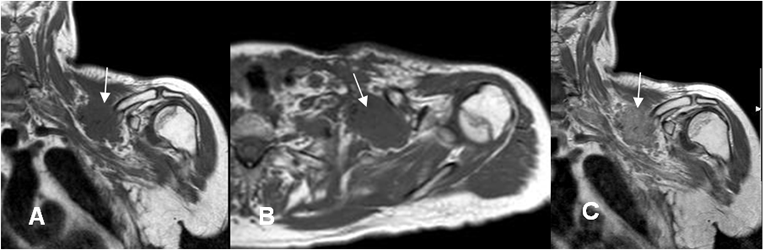

Fig 9 C. Cambios post radioTx.

A: RM axial simple y B: RM axial con contraste. Igual paciente anterior. Alteración de la pared torácica anterior, por cambios Qx. Reemplazo de la grasa que rodea las raíces del plejo braquial, la cual realza con el contraste, por fibrosis secundaria.